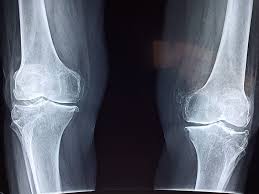

콘드로이친은 연골을 구성하는 주요 성분 중 하나로, 우리 몸의 관절과 연골 조직에 자연적으로 존재하는 물질입니다. 특히 연골의 탄력과 수분 유지에 관여해 관절이 부드럽게 움직일 수 있도록 돕는 역할을 합니다. 나이가 들수록 체내 콘드로이친 함량이 감소하면서 연골 마모와 관절 불편감이 점차 나타날 수 있습니다.

콘드로이친은 연골 조직 내에서 수분을 끌어당기는 성질을 가지고 있어, 연골의 탄력 유지에 도움을 줍니다.이로 인해 관절이 움직일 때 발생하는 충격을 완화하고, 연골 손상을 간접적으로 줄이는 역할을 기대할 수 있습니다. 이러한 작용은 개인 차가 크기 때문에, 효과를 체감하는 시기와 정도는 사람마다 다를 수 있습니다.